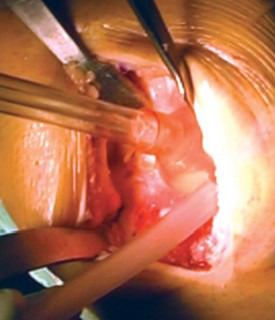

Cementing Technique and Implant Implantation

The hallmark of a cemented TKA is the creation of a durable, interlocking micro-mechanical bond between the host trabecular bone and the polymethylmethacrylate (PMMA) bone cement. PMMA is not an adhesive; it functions as a grout. Therefore, meticulous bone bed preparation is the single most critical factor in preventing aseptic loosening. The resected bony surfaces must be aggressively cleansed using pulsatile lavage to remove marrow, fat, and debris, exposing the porous cancellous bone. Sclerotic areas should be perforated with a small drill bit to enhance cement interdigitation.

The bone must be thoroughly dried immediately prior to cement application. High-viscosity cement is typically mixed under a vacuum to reduce porosity and increase fatigue strength. The cement is applied during its "doughy" phase to both the implant surfaces and the prepared bone. The components are then impacted into place.

Crucially, the cement must be pressurized into the cancellous bone to achieve a penetration depth of 3 to 4 mm. Once the components are seated, all extruded peripheral cement must be meticulously removed with a curette, particularly from the posterior aspect of the condyles and the posterolateral corner, where retained cement fragments can cause severe postoperative pain, third-body wear, or impingement. The knee is then held in full extension with axial compression applied until the exothermic polymerization process is complete and the cement is fully cured.